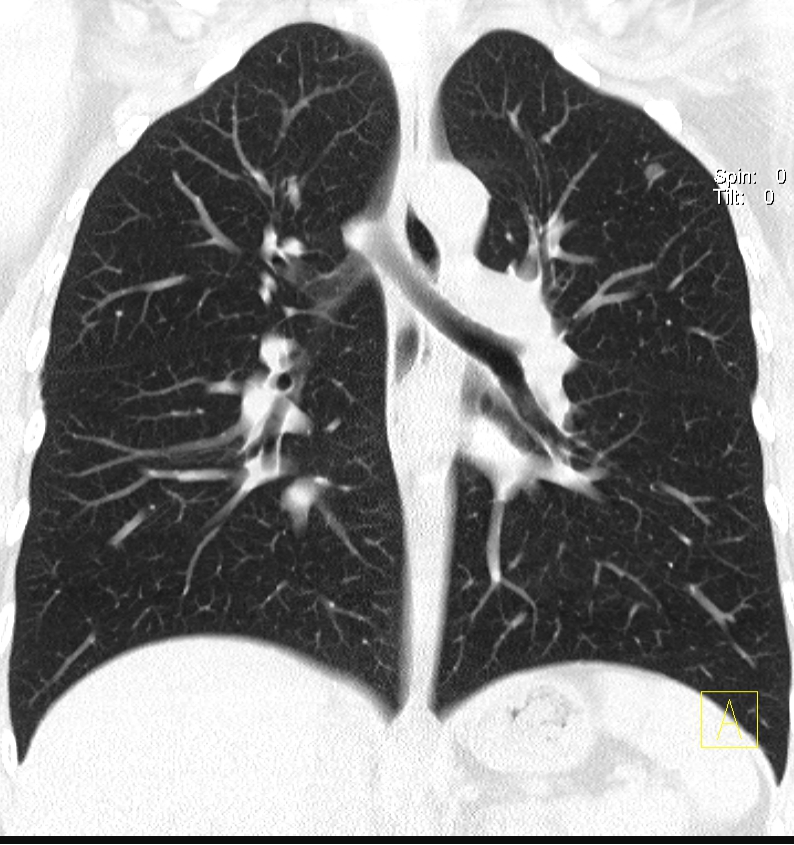

四、呼吸系统成像更精细

可以完美显示支气管树、肺血管、肺内病灶及相关毗邻关系等,对支气管扩张、肺气肿、肺内小结节、肺癌的诊断等都有独特的价值。